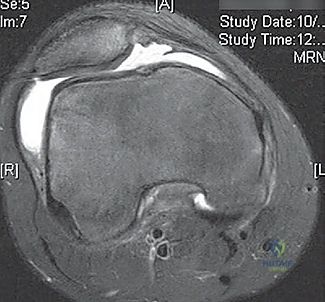

- MRI Scan: Highly recommended for all patients with a large traumatic effusion due to the high rate of occult articular or osteoarticular injury.

* Osteochondral Lesions: Crucial for determining size, location, and potential for repair versus removal.

* Bone Bruise Pattern: Confirms patellar dislocation (medial patella and lateral femoral condyle).

* Anatomical Risk Factors: Assesses patella alta, trochlear dysplasia, tibial tubercle-trochlear groove (TT-TG) distance.

* Bone Bruises: MRI often reveals increased signal on the medial patella and the midportion of the lateral femoral condyle. This distinct pattern helps differentiate it from ACL tears.